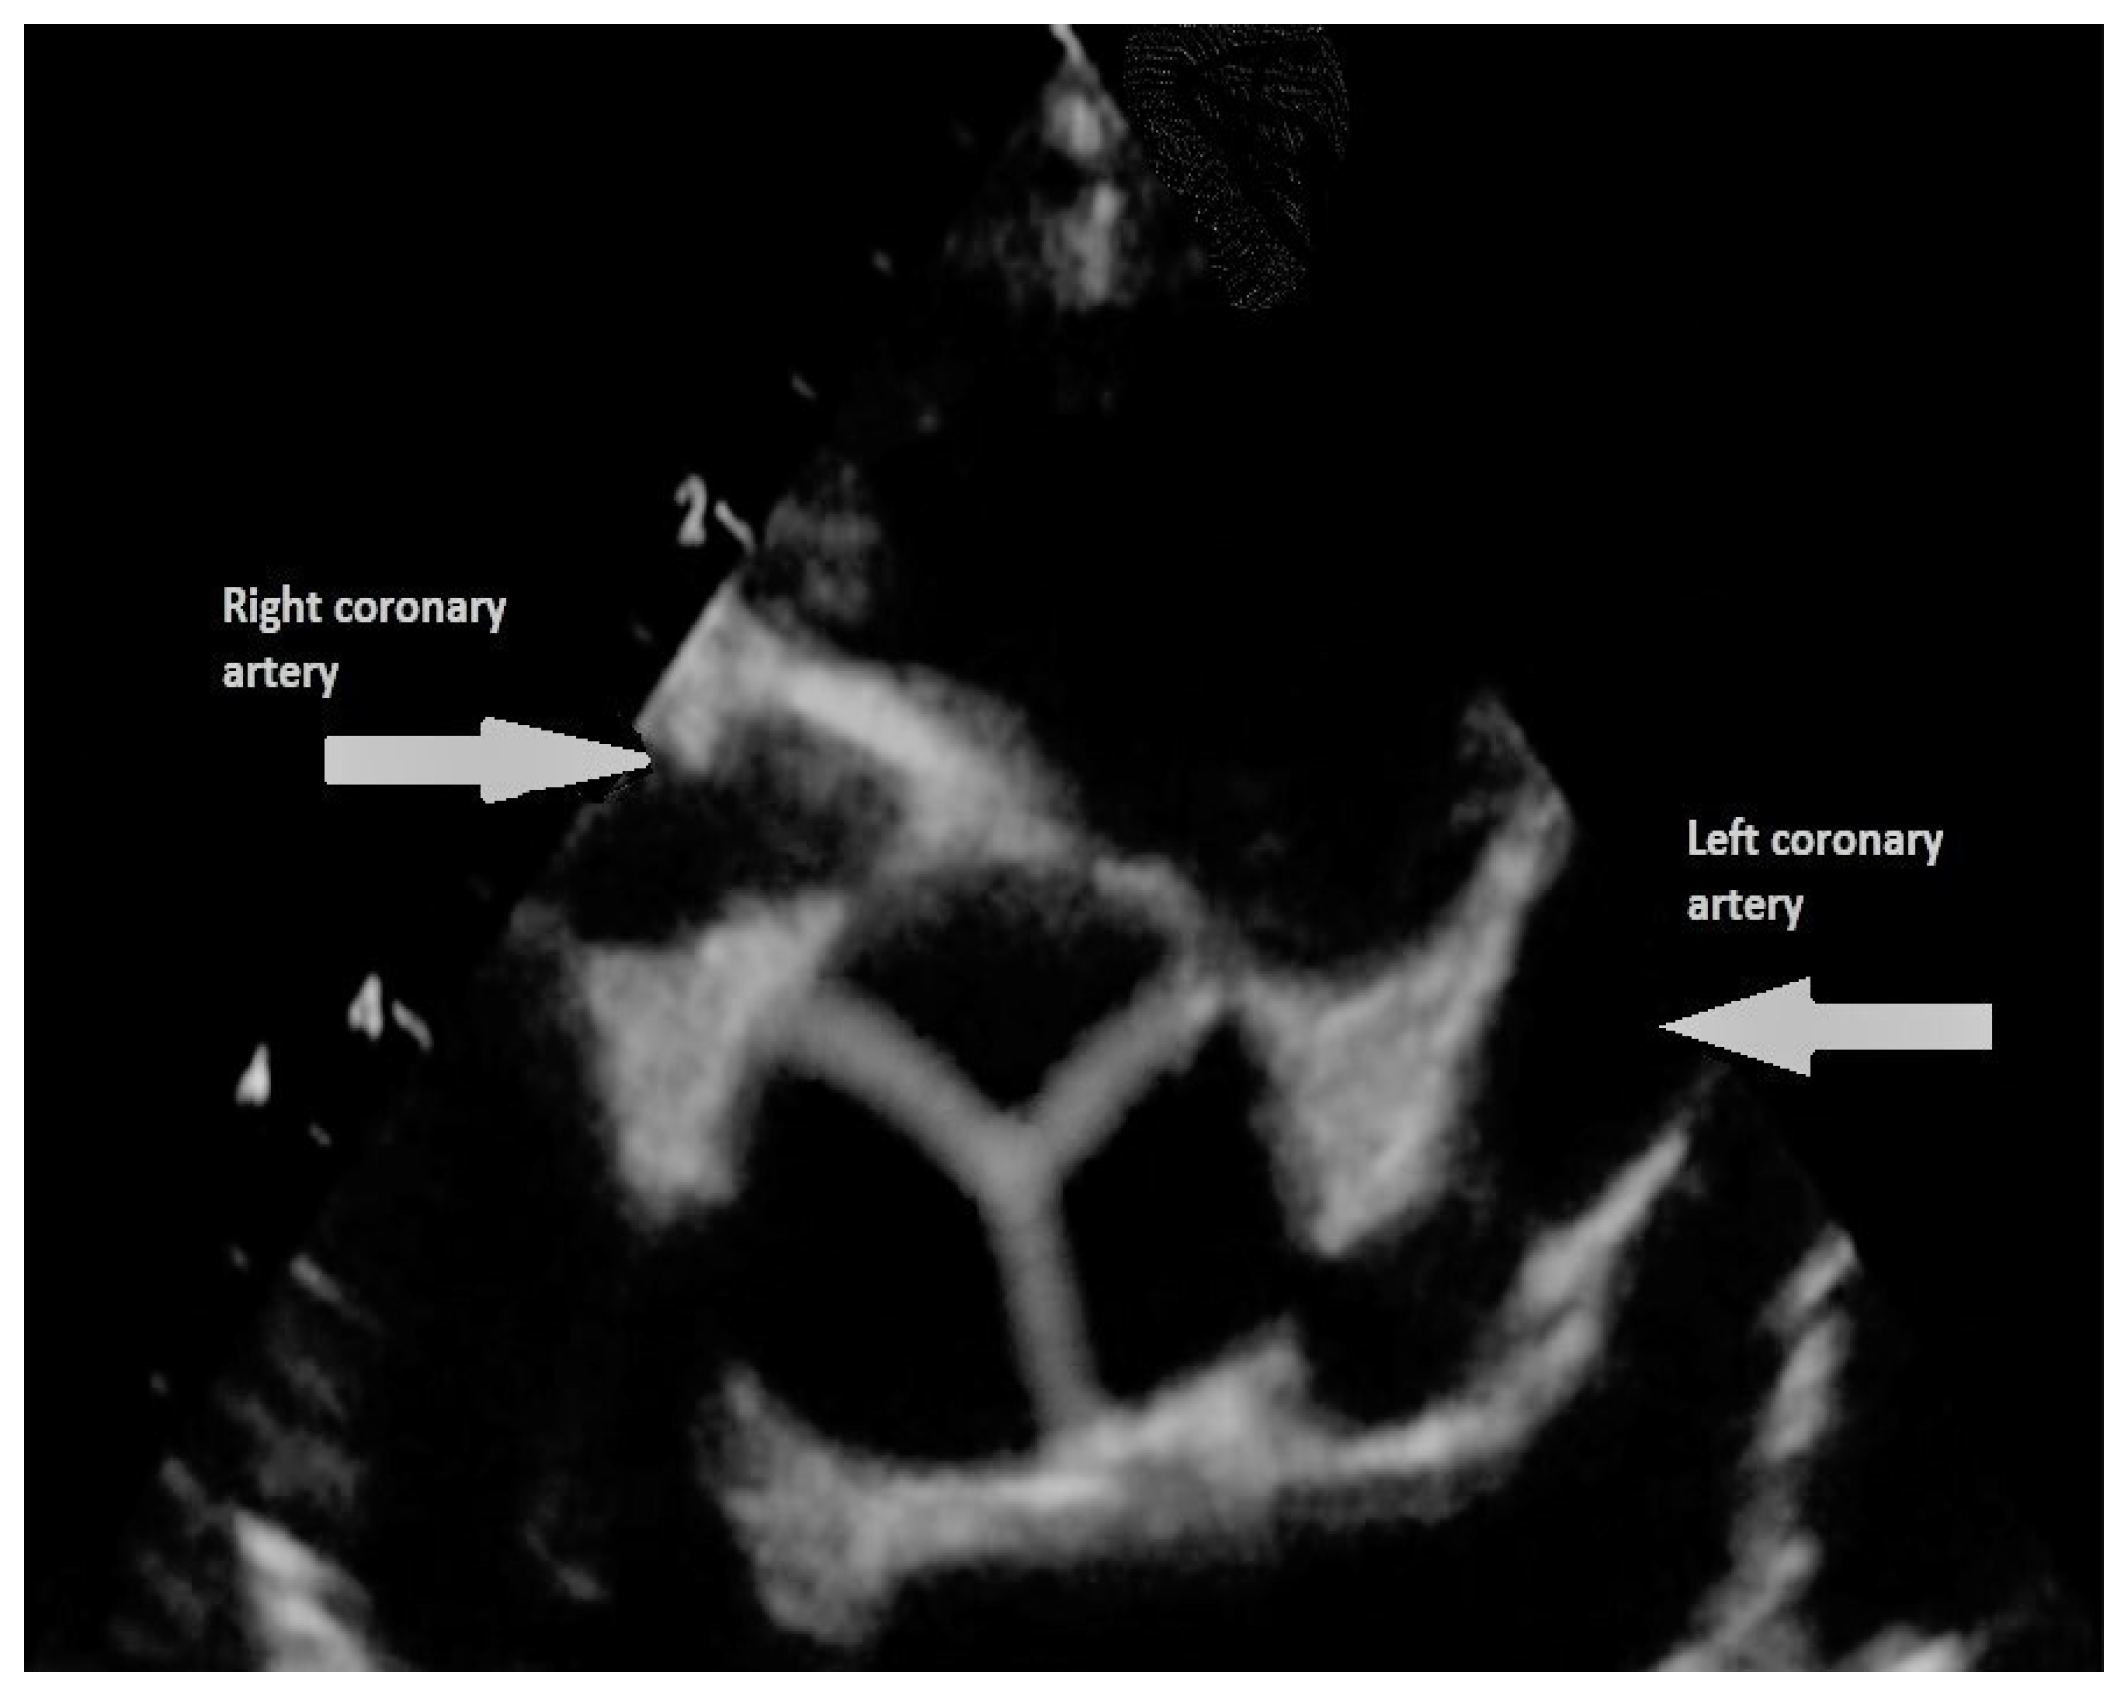

- Patel, S.G.; Frommelt, M.A.; Frommelt, P.C.; Kutty, S.; Cramer, J.W. Echocardiographic diagnosis, surgical treatment, and outcomes of anomalous left coronary artery from the pulmonary artery. J. Am. Soc. Echocardiogr. 2017, 30, 896–903. [Google Scholar] [CrossRef]